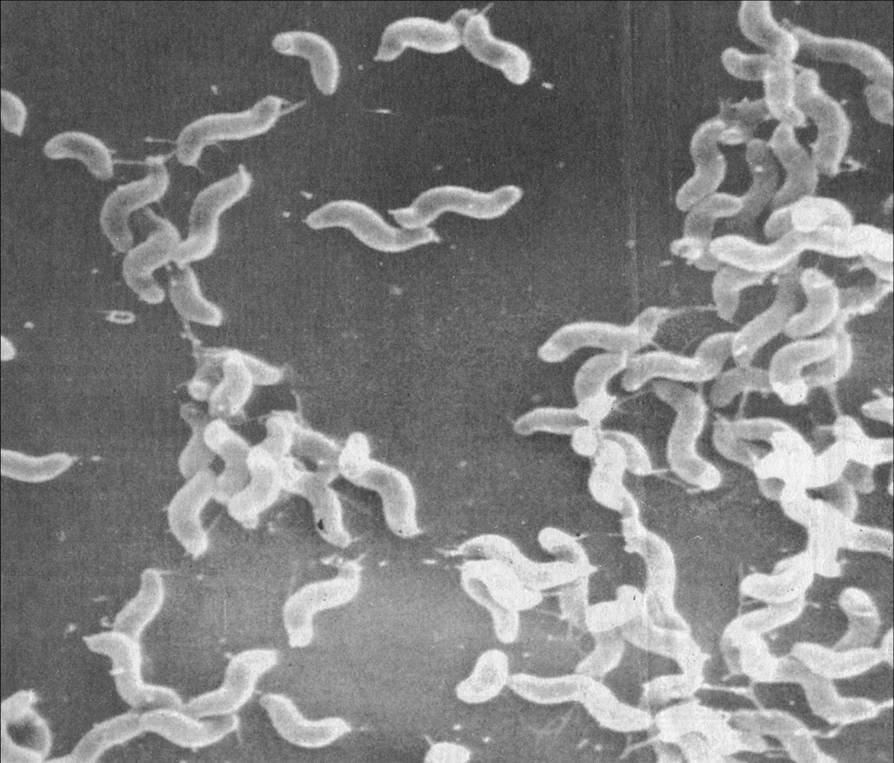

Кампилобактер фетус: патогенез и инфекции

/evrimagaci.org%2Fpublic%2Fcontent_media%2Fb099374a4578fc241a0555a594831216.jpeg)